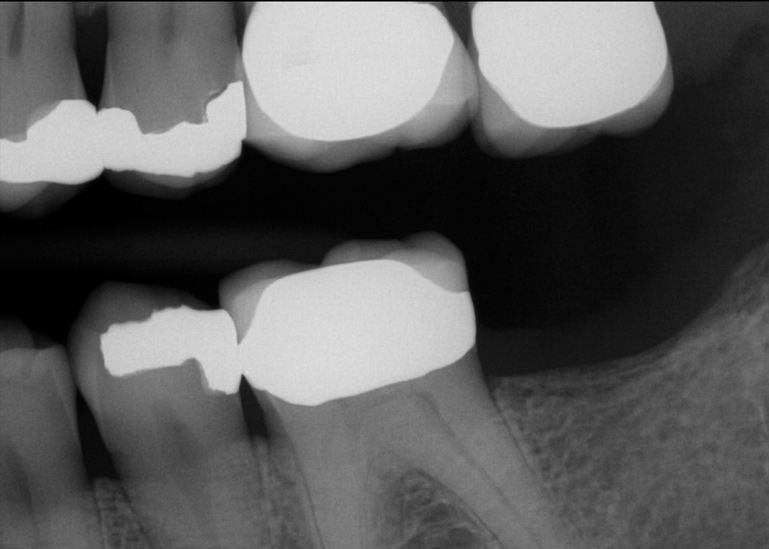

Another consideration is mean vertical displacement of unhampered posterior teeth, which in some studies was minimal: 0.8 mm37 and 0.9 mm30 (Table 1). Yet, there could have been sites where the amount of extrusion was clinically relevant. When Lindskog-Stokland et al assessed the risk of over-eruption using 1 mm as a threshold, they stated there was an odds ratio of 3.3 that unimpeded molars would extrude 1 mm compared to opposed molars.30 Based on their calculations, however, it is unclear which patients with a missing molar are at risk of over-eruption (Figure 1 through Figure 4). Indeed, if susceptible individuals could be identified, then restorative therapy could be initiated to stabilize their occlusion (eg, tooth replacement). Furthermore, odds ratios can be highly misleading, and predictive values would provide clinicians a better perspective as to what percentage of sites may experience significant extrusion.41,42

Fig 1. In 2009 patient No. 1 presented with a missing tooth at site No. 31.

Figure 1

Fig 2. In 2016 patient No. 1 manifested no alterations of tooth position No. 2.

Figure 2

Fig 3. Patient No. 1, contralateral side; in 2009 patient presented with teeth Nos. 15 and 18. Subsequently, tooth No. 18 was extracted due to tooth fracture.

Figure 3

Fig 4. Patient No. 1 in 2016, with extrusion of tooth No. 15. Two different experiences in the same mouth, as shown in Figs 1–2 and Figs 3–4, underscore the unpredictability of extrusion.

Figure 4